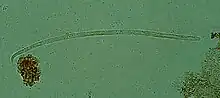

Onchocerca volvulus, the causative agent of river blindness | |

Onchocerca volvulus is a filarial (arthropod-borne) nematode (roundworm) that causes onchocerciasis (river blindness), and is the second-leading cause of blindness due to infection worldwide after trachoma. It is one of the 20 neglected tropical diseases listed by the World Health Organization, with elimination from certain countries expected by 2025.[2]

O. volvulus parasites obtain nutrients from the human host by ingesting blood or by diffusion through their cuticle. They may be able to trigger blood-vessel formation because dense vascular networks are often found surrounding the worms.[6] They are distinguished from other human-infecting filarial nematodes by the presence of deep transverse striations.[7]

It is a dioecious species, containing distinct males and females, which form nodules under the skin in humans. Mature female worms permanently reside in these fibrous nodules, while male worms are free to move around the subcutaneous tissue. The males are smaller than females, with male worms measuring 23 mm in length compared to 230–700 mm in females.[7]

The release of oocytes (eggs) in female worms does not depend upon the presence of a male worm, although they may attract male worms using unidentified pheromones.[8] The first larval stage, microfilariae, are 300 μm in length and unsheathed, meaning that when they mature into microfilariae, they exit from the envelope of the egg.[9]